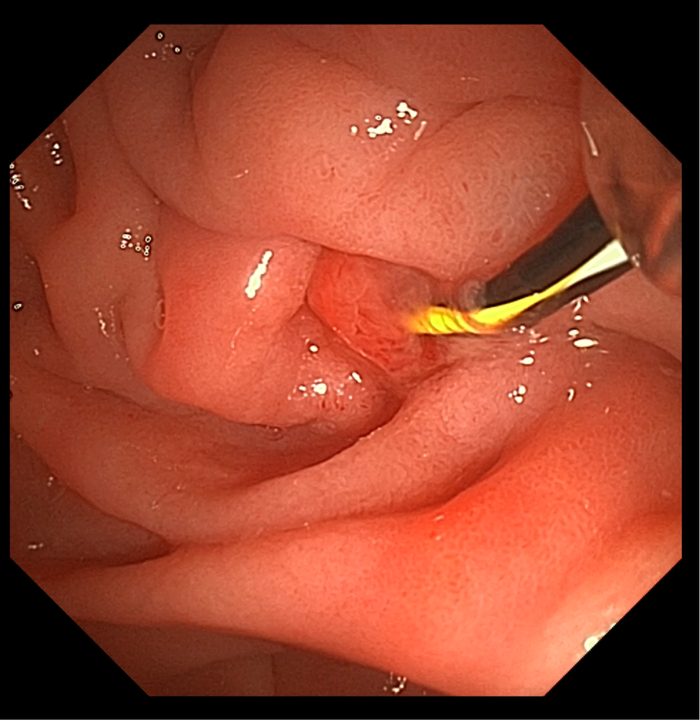

患者男,56岁,十二指肠镜提示慢性胰腺炎,CT下显示胰管结石。

CT下可见,结石狭窄处

导丝已插入胰管(右上

由此病例可见,即使是面对高难度的双导丝技术胰管内取石,澳华全新UHD系列十二指肠镜仍然可以凭借良好的操控性能,让医者诊疗时十分得心应手。且在更大的抬钳器角度的匠心设计下,医生可以更轻松、准确地插入耗材,大幅缩短手术时间。